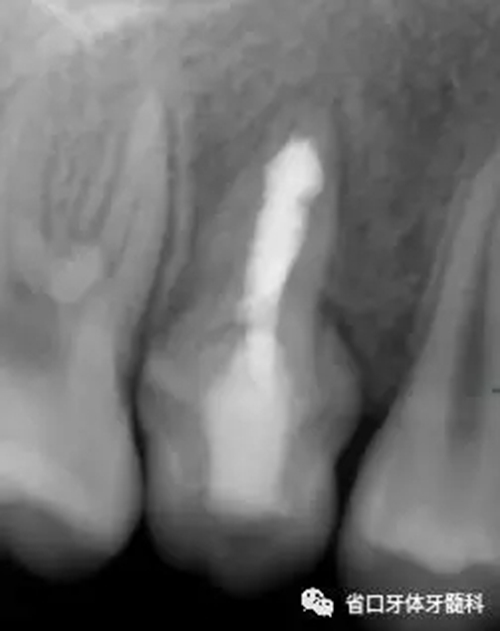

圖6 根管充填后